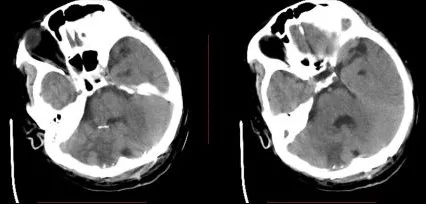

术后CT

术后呼吸机支持治疗3周后脱机,GCS 15,双侧肢体自主活动,出院康复。